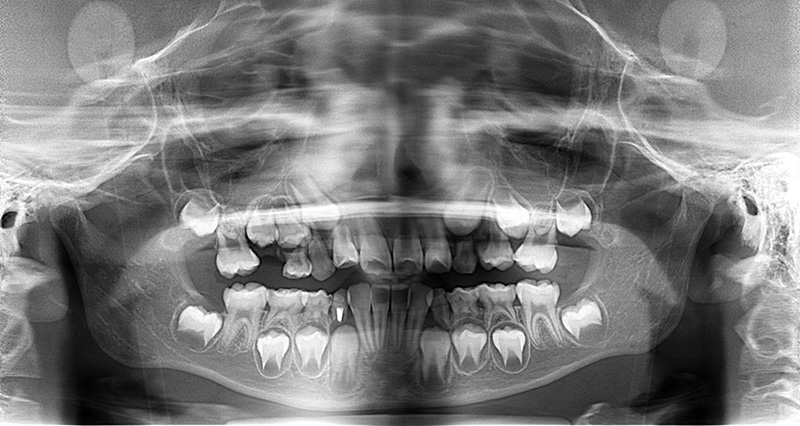

| X-Ray所見 | |

| パノラマ所見 | 上顎両側6、特に左側6は近心傾斜が認められ、両側5の萌出スペース不足が認められた。 |

| 批評・予后 | 早期に6の遠心移動を行いナンスのホールディングアーチにて保隙をした結果、5は良好な状態で萌出できたように思う。 今後は永久歯列完成まで経過観察を行っていく予定である。 |